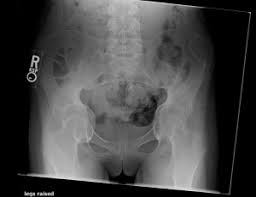

Marfan syndrome back pain. Despite these limitations studies describe that the prevalence of pain in patients with MFS is high varying from 47 to 92 and affecting several anatomic sites. Each had evidence of expansion of the central sacral spinal canal and enlargement of sacral foramina associated with extensive bony erosion. Low Back Pain in Marfan syndrome Patient Background and Purpose Marfan Syndrome MFS is an autosomal dominant disorder secondary to mutation of Fibrillin-1 that affects the bodys connective tissue.

Click below to download. Three patients complained of low back pain. MFS primarily affects the cardiovascular musculoskeletal and ocular systems.

Skeletal manifestations in the Marfan patient may develop or become more pronounced with age. The correlation between dural ectasia and back pain is uncertain.

Each had evidence of expansion of the central sacral spinal canal and enlargement of sacral foramina associated with extensive bony erosion. Three patients complained of low back pain. Experience Instant Relief From Back Pain With This New Product. Dural ectasia may cause low back and leg pain abdominal pain and headaches. A review of their medical history revealed that they had been diagnosed with Marfan Syndrome some years earlier. Not everyone who has spondylolisthesis also has Marfan syndrome but the likeliness of developing it is much higher for anyone who experiences this syndrome. It was descending down my anus and blocking my back passage so trying to empty my bowels was turning into a struggle which felt like an Olympic sport.